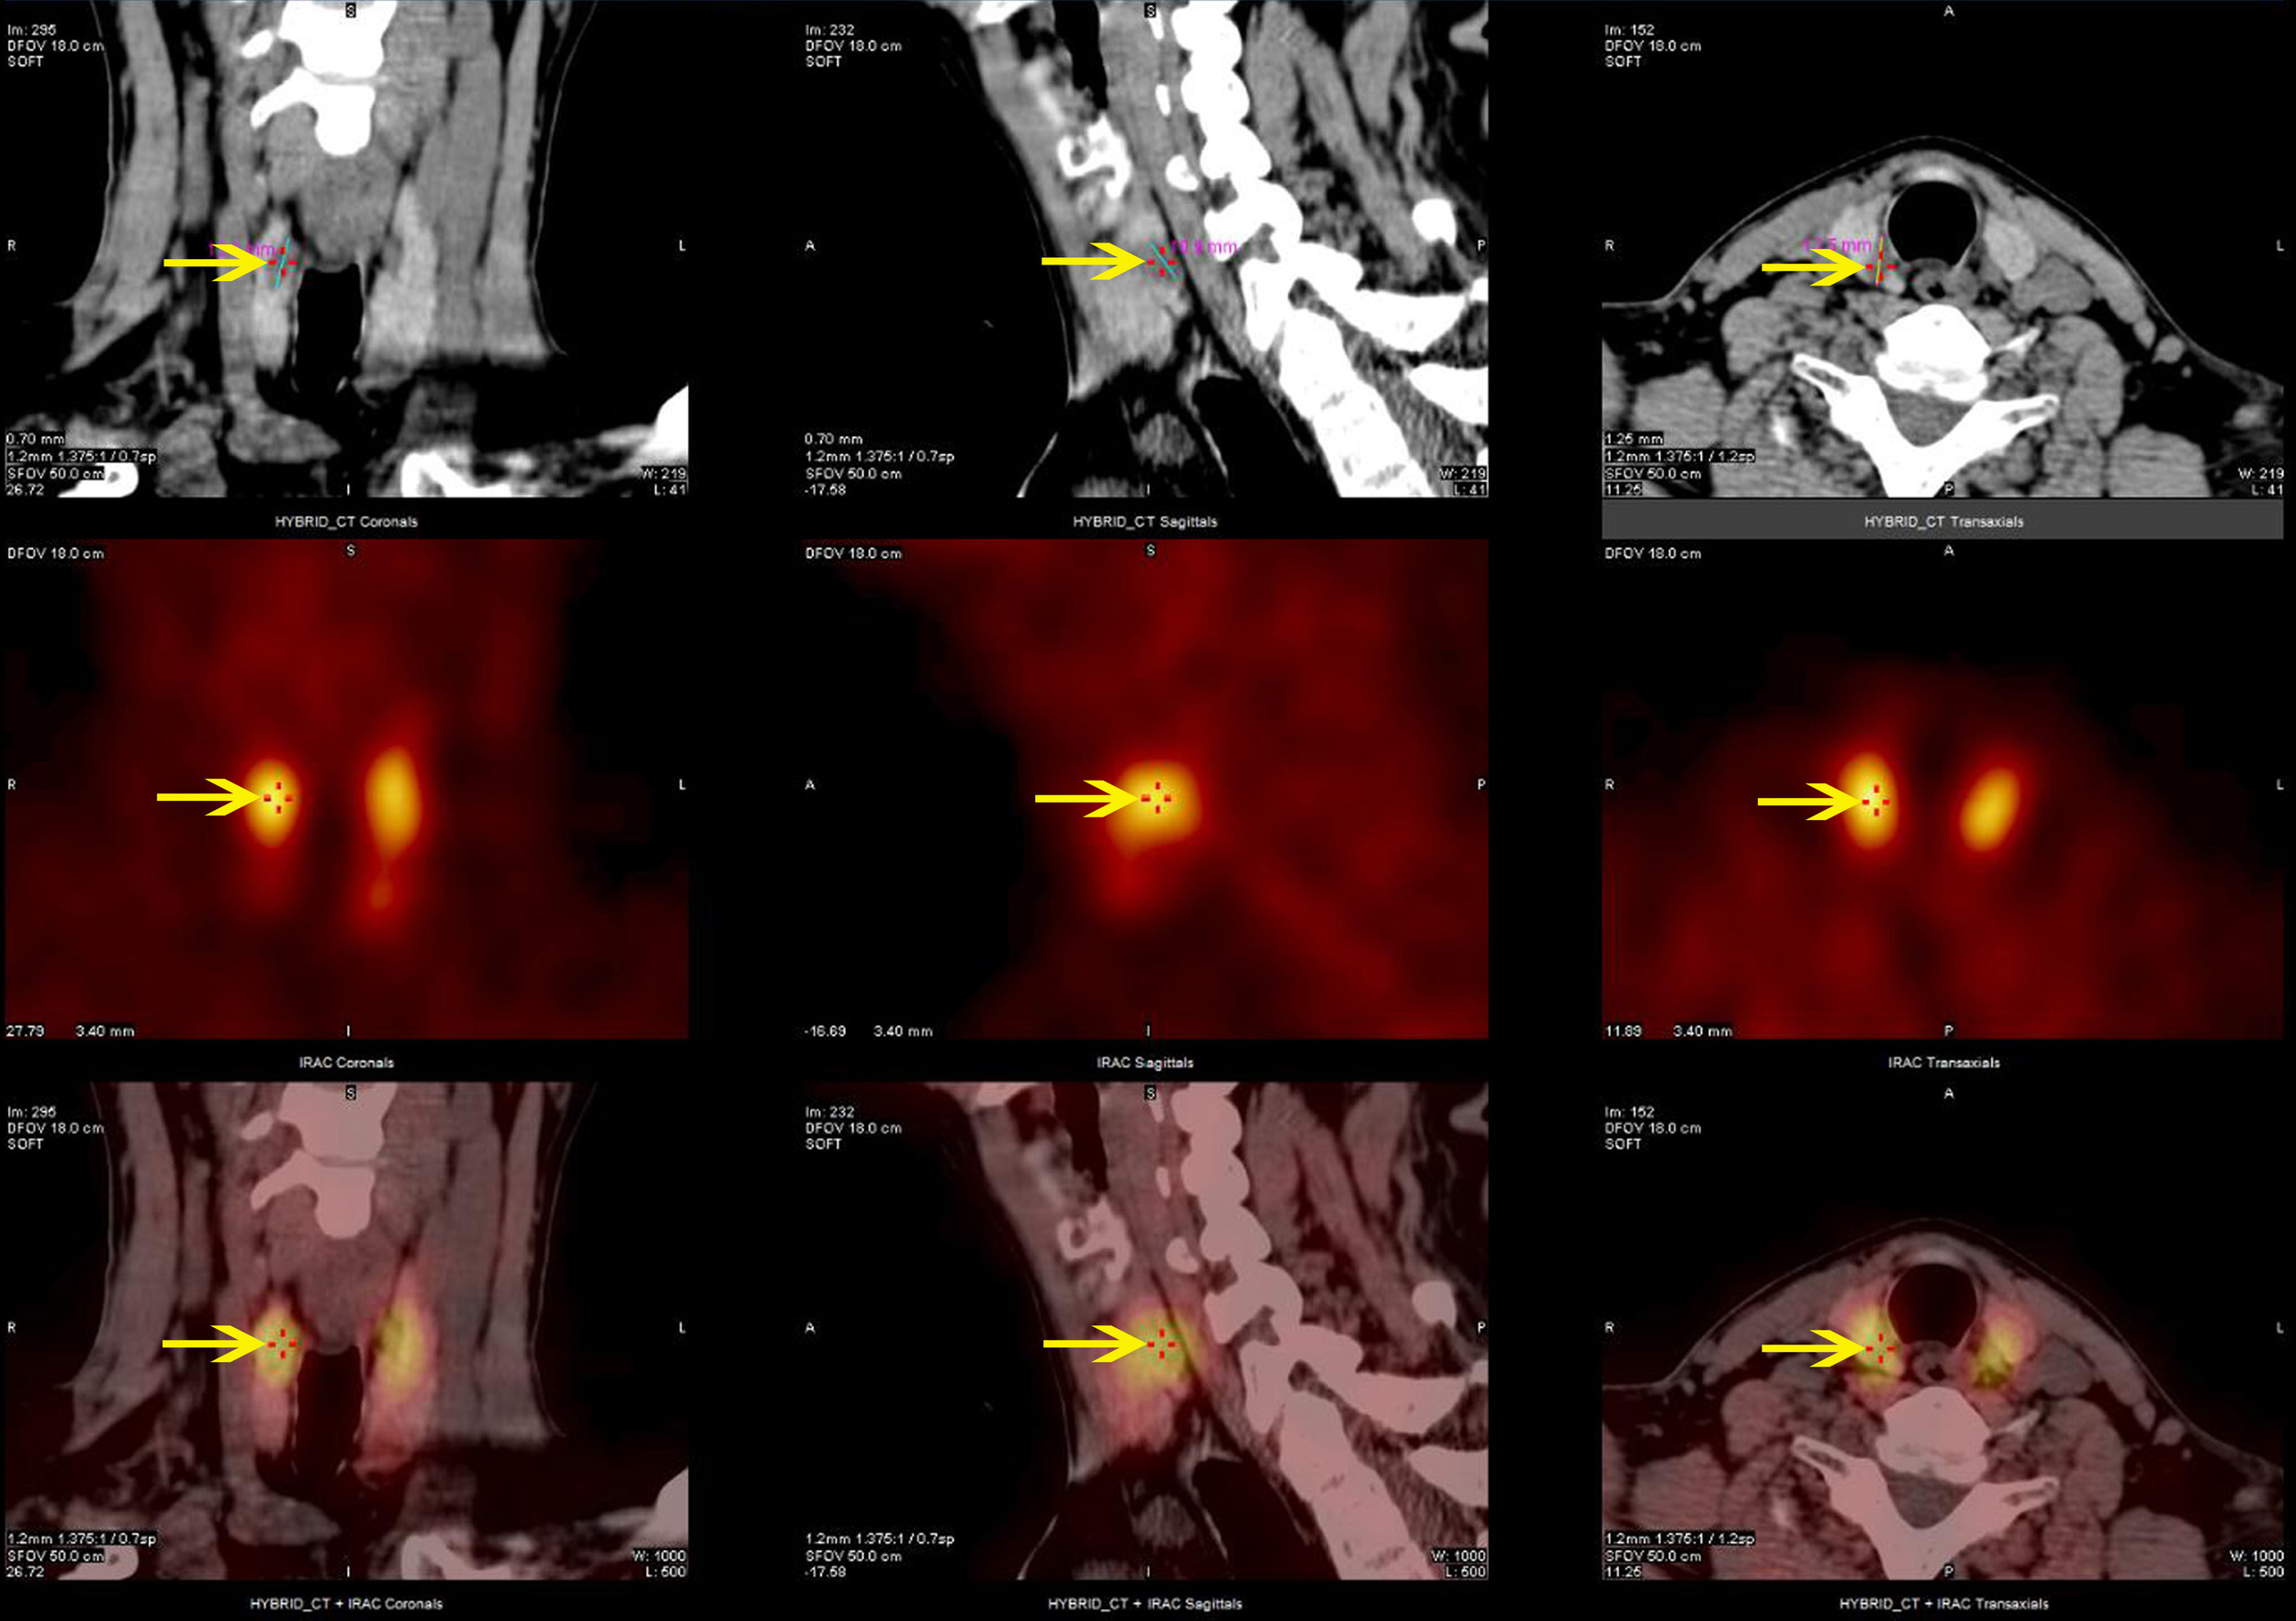

MEN1 gene testing was performed on the index case’s parents. The father carried the same gene change, also as a heterozygote(Figure 3B), and the mother was wild type (Figure 3C). The father, a 43-year-old male with a history of recurrent back pain for over 6 years, had undergone multiple procedures for bilateral ureteral stones, including extracorporeal shock wave lithotripsy and transurethral ureterolithotomy, with postoperative analysis confirming the stones as calcium oxalate. Physical examination revealed no positive findings. Further tests showed parathyroid hormone (PTH) at 24.28 pmol/L, blood calcium at 2.77 mmol/L, serum inorganic phosphorus at 0.67 mmol/L, and fasting blood glucose at 5.67 mmol/L. A 24-hour urine electrolyte analysis indicated calcium at 4.38 mmol/24h and phosphorus at 16.20 mmol/24h. Bone metabolism markers suggested a significant increase in bone turnover. Gastrin, pituitary and target gland axis hormones, blood and urine catecholamines and their metabolites, aldosterone-renin-angiotensin system, fasting blood glucose, insulin, C-peptide, complete blood count, liver and kidney function, urinalysis, and tumor markers were all normal. Enhanced MRI of the pancreas and pituitary MRI showed no definitive abnormalities. Parathyroid SPECT/CT hybrid imaging revealed mild increased MIBI uptake in a nodule behind the lower part of the right thyroid lobe, suggesting parathyroid tissue origin (Figure 4). On July 9, 2019, a neck exploration and resection of the right lower parathyroid adenoma were performed, in line with the patient’s preference against subtotal parathyroidectomy. Pathology indicated adenomatous hyperplasia of the right lower parathyroid, with immunohistochemistry showing PTH (+), CD56 (-), Syn (+, partial), CgA (+), and a Ki-67 positivity rate of approximately 1-2%, special staining for reticular fibers (Foot) was positive. Postoperative reevaluation showed blood calcium at 2.51 mmol/L and phosphate at 0.95 mmol/L. Follow-up to the present day, February 18, 2024, shows the father with normal blood calcium, phosphate, PTH levels, no further episodes of urinary tract stones, and no emergence of other MEN1-associated disease phenotypes.

Figure 4

Parathyroid SPECT/CT hybrid imaging of the proband’s father: nodular parathyroid imaging is observed in the posterior aspect of the lower pole of the right thyroid lobe, with mildly increased MIBI uptake.